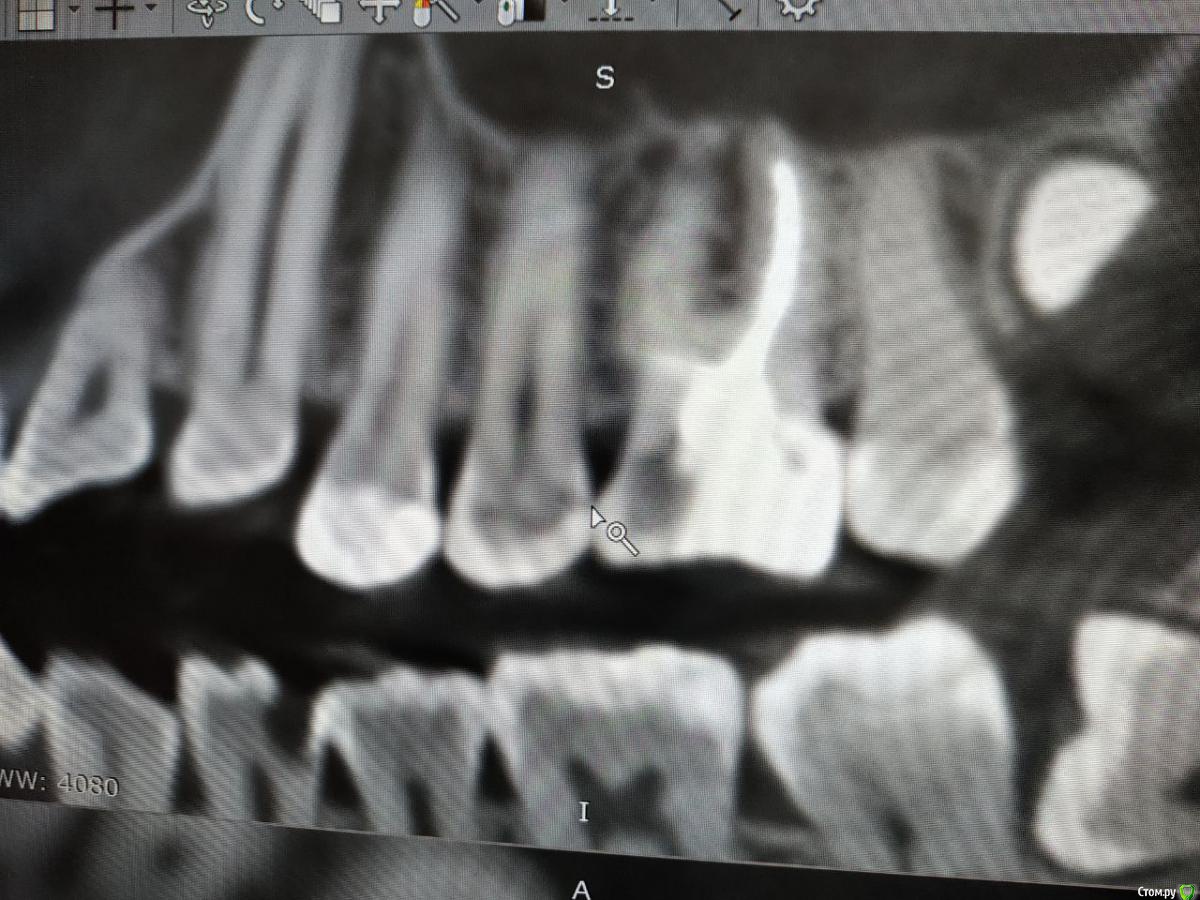

red_butler Опубликовано 4 февраля, 2020 Поделиться Опубликовано 4 февраля, 2020 Покажите ещё срезы Кт Ссылка на комментарий

Liza544 Опубликовано 4 февраля, 2020 Автор Поделиться Опубликовано 4 февраля, 2020 Вот еще пару снимков которые у меня есть. ПРошу заметить, что последние 4 снимка (файлы 7-10), которые я тут прикрепила - до пломбы на 25-м зубе и до залеченного 4-го канала в 26-м зубе. Подскажите пожалуйста, может ли быть зуб недостаточно залечен, хотя на КТ ничего подозрительного не видно? Ссылка на комментарий

ЛанаМ Опубликовано 4 февраля, 2020 Поделиться Опубликовано 4 февраля, 2020 Воспаление десны может давать постоянные ноющие боли и боль при накусывании. От чистки сразу не пройдет, нужно дней 5-7 противоспалительного лечения и отсутствие травмирования (постараться ниткой не чистить). Также нужно убедиться, что нет хронического воспаления в гайморовой пазухе. Побольше срезов кт, желательно уже после пломбирования четвертого канала. Да, бывают проблемы в зубе и при идеальной картинке рентгеновского снимка. На нем видны только крупные каналы, а там еще целая сеть мелких. Ссылка на комментарий